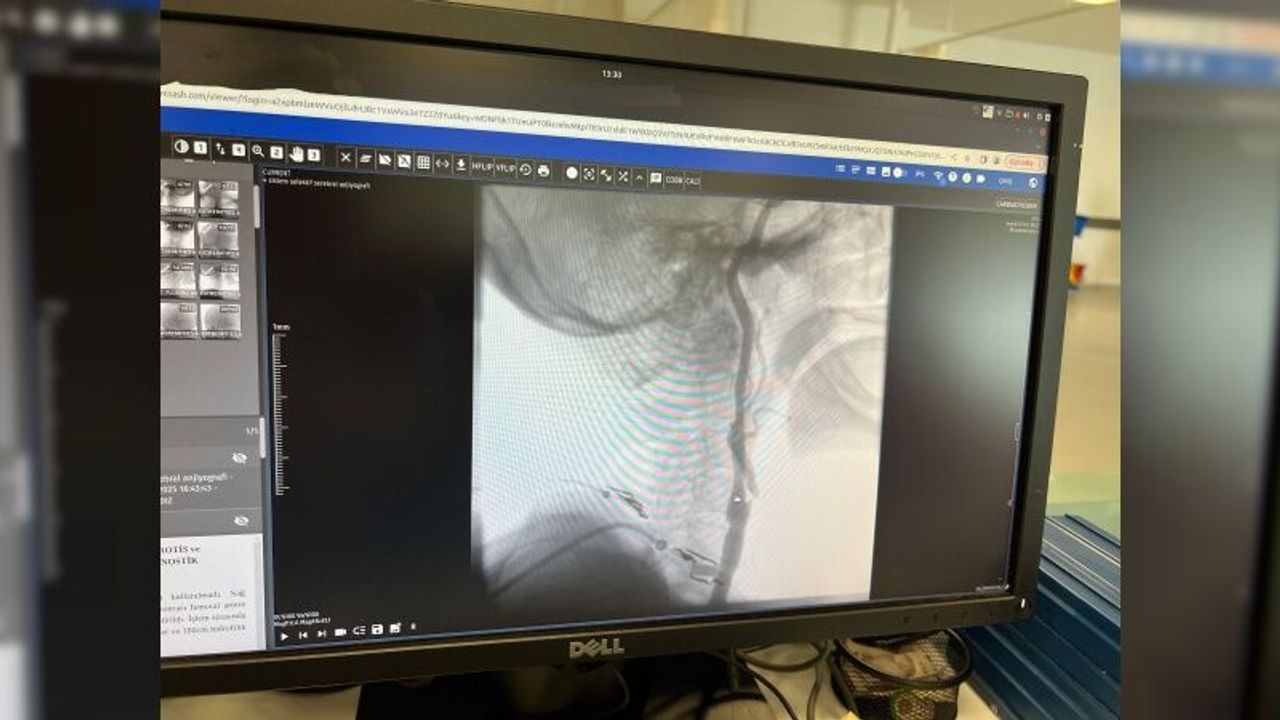

Şah damarındaki daralmaları açmanın iki yöntemi olduğunu ifade eden Girişimsel Kardiyoloji Uzmanı Doç. Dr. Ramazan Gündüz ise şunları söyledi: "Boyun damarlarını açma işlemi iki şekilde yapılabilir. Bir karotis endarterektomi dediğimiz ameliyatla bir diğer yöntem ise perkutan girişim dediğimiz stent yöntemiyle açılabilir. Biz kliniğimizde nöroloji ve kardiyoloji olarak bir konsey yapıyoruz. Damarı ciddi tıkalı olan ve buna bağlı felç geçirmiş hastalarda bu konseyde hastaya işlem yapıp yapmama kararı veriyoruz. Verdiğimiz karar çerçevesinde eğer hastaya işlem kararı vermişsek femoral arter dediğimiz kasık arterinden bir şitle 6 ya da 7 F çapında bir şitle ince bir boruyla bu damara giriş yapıyoruz ve boyun damarlarına ulaşıyoruz. Özellikle teller, filtreler ve stentlerle bu damarları açıp hastanın tedavisini gerçekleştiriyoruz. İşlem ameliyatsız olduğu için hastamız ertesi gün rahat bir şekilde problem olmazsa işlemde taburcu olabiliyor bu işlemden sonra. Bu işlemin yapılması için özellikle anjiografinin olduğu girişimsel nöroloji uzmanının ve girişimsel kardiyoloji uzmanının olduğu ve bu konuda yeterli vaka tecrübesine ve deneyime sahip uzmanların olduğu merkezler gerekir. Bunu yapabilmek için belli bir vaka sayısına ulaşmak ve bu konuda tecrübeli olmak gerekiyor. Biz de Manisa Şehir Hastanesi’ndeki girişimsel kardiyoloji ve nöroloji uzmanları olarak bu işlemi kliniğimizde efektif bir şekilde gerçekleştiriyoruz."